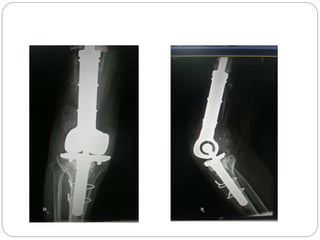

This document discusses 8 oncology cases. Case 1 involves a 40-year old female with right knee pain. Case 2 is a 28-year old male with a left subtrochantric fracture from a MVA who is now experiencing increasing left knee pain and swelling. Biopsy results showed high-grade osteosarcoma. Case 3 is a 30-year old female with breast cancer and bone metastases causing bilateral hip pain.